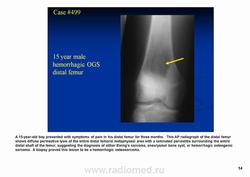

Телеангиэктатическая остеосаркома - редкий (составляет около 4% всех остеосарком) вариант остеосаркомы, характеризующийся наличием кист, заполненных кровью. При рентгенологическом исследовании обычно выявляется полностью литическое поражение без признаков склерозирования, интенсивное вздутие кортикальной пластинки и ее деструкция, часто обнаруживаются периостальная реакция и распространение патологического процесса в мягкие ткани. Гистологическая диагностика телеангиэктатического варианта остеосаркомы может быть относительно несложной при наличии атипичного остеогенеза и высокой степени анаплазии клеточных элементов. Однако довольно часто, особенно у детей и подростков, диагностика вызывает значительные трудности, так как эта остеосаркома, в основном, представлена высокодифференцированным вариантом. Последний отличается тем, что опухолевые клетки определяются только в области выстилки кист и полостей опухоли, злокачественные клетки характеризуются низкой степенью анаплазии, опухолевый остеоид обнаруживается лишь при целенаправленном исследовании серийных срезов, встречаются участки ткани, в которых клеточные элементы и остеоид не имеют признаков атипизма и микроскопическая картина полностью соответствует аневризмальной кисте кости, в связи с чем не исключена диагностическая ошибка при исследовании небольшого количества материала, особенно биопсийного. Относительно медленное развитие опухоли, обычно чисто литическое поражение кости, сходство рентгенологической картины с аневризмальной кистой или гигантоклеточной опухолью кости также способствуют постановке неверного диагноза.

Клиническая картина. Схожа с обычной остеосаркомой: болезненность и отёчность в области опухоли; в связи с массивным разрушением кости довольно часто (до 25% случаев) определяется патологический перелом.

Рентгенологически выявляют метафизарную локализацию, полностью литическое поражение без признаков оссификации, часто интенсивное вздутие кости и её деструкцию, формирование мягкотканого компонента, иногда периостальную реакцию.